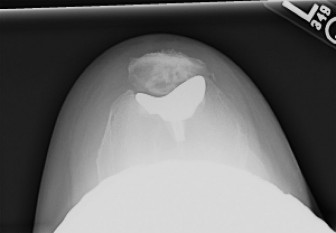

A 48-year-old female patient presents with anterior left knee pain. She has had a history of recurrent patell…